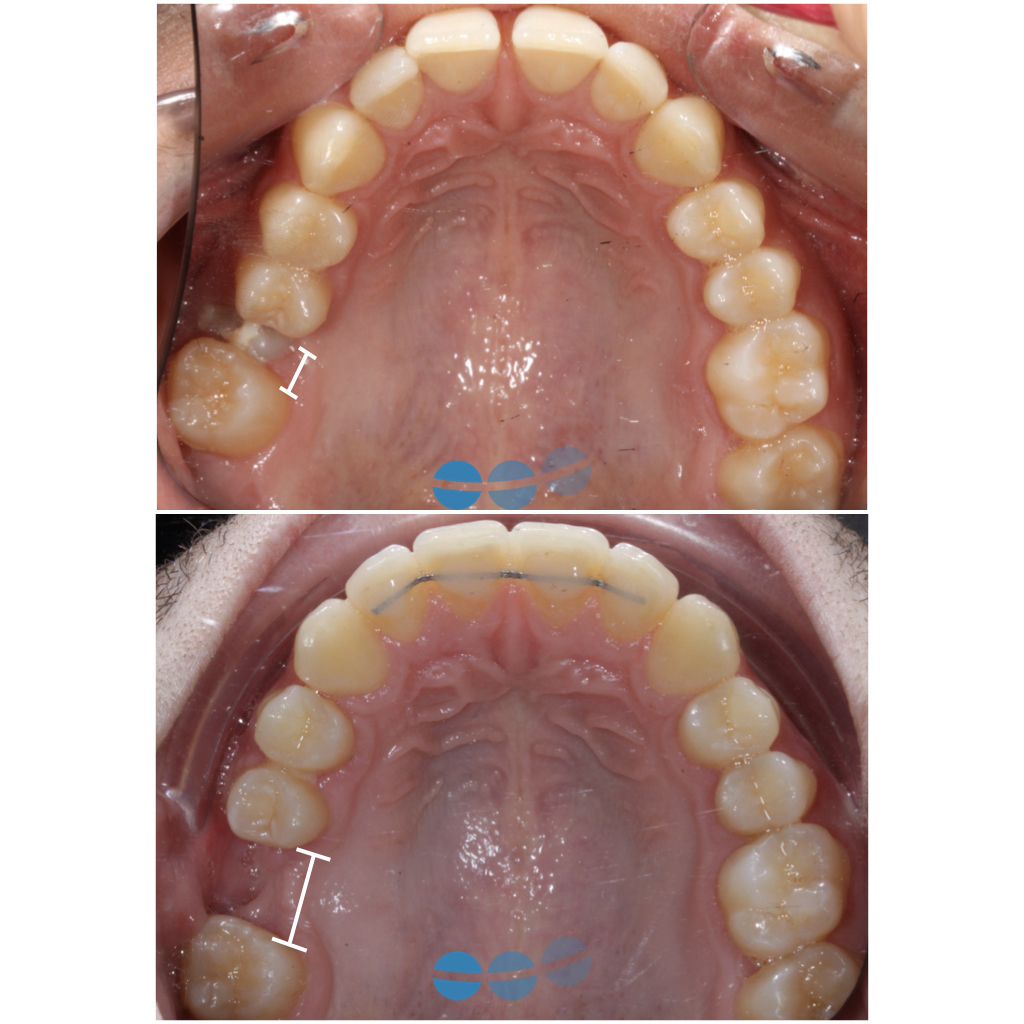

NUUMOON En images Arrêt des parafonctions (lolette, pouces, etc…) Orthodontie pédiatrique Orthopédie dento-faciale Apnée du sommeil de l’enfant (TROS) Esthétique du sourire Orthodontie et Articulation Temporo Mandibulaire (ATM) Traitement combiné ortho-chirurgicaux Traitements pluridisciplinaires Arrêt des parafonctions Effet de la lolette sur les dents Effet du pouce sur les dents Position de la langue et impact sur les dents Mieux respirer pour mieux grandir Respiration et santé Respiration et santé Sans titre.004 Orthodontie pédiatrique Conséquences ventilation orale – nuumoon ChatGPT Image 5 sept. 2025, 09_00_25 conséquences posturales de la ventilation orale Prévention canine incluse Prévention canine incluse Prévention canine incluse Dents qui s’emboitent à l’envers Dents qui s’emboitent à l’envers orthopédie dento-faciale Traitement déformation mâchoire Déformation des mâchoires : menton en avant Déformation des mâchoires : menton en avant Déformation machoire Déformation machoire Déformation machoire : machoire du bas en arrière Déformation des mâchoires : menton en avant Déformation des mâchoires : menton en avant Posture dents et mâchoire Anomalie de la mâchoire Apnée du sommeil orthodontie invisible à Genève Aligneurs transparents & bagues linguales – l’art de corriger sans rien laisser paraître Troubles de l’articulation temporo-mandibulaire et bruxisme Chirurgie orthognathique Traitements pluridisciplinaires INSIGHTS Contenu pour les enfants